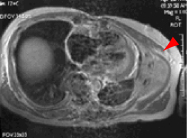

●図2-c |